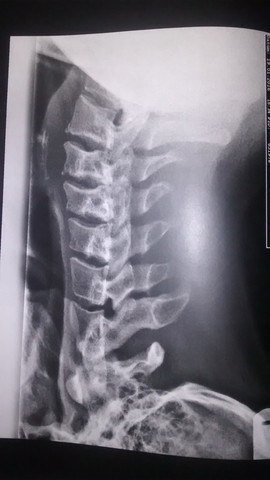

Weisse Flecken Auf Rontgenbild Von Halswirbelsaule Was Kann Das Sein Hals Rontgen